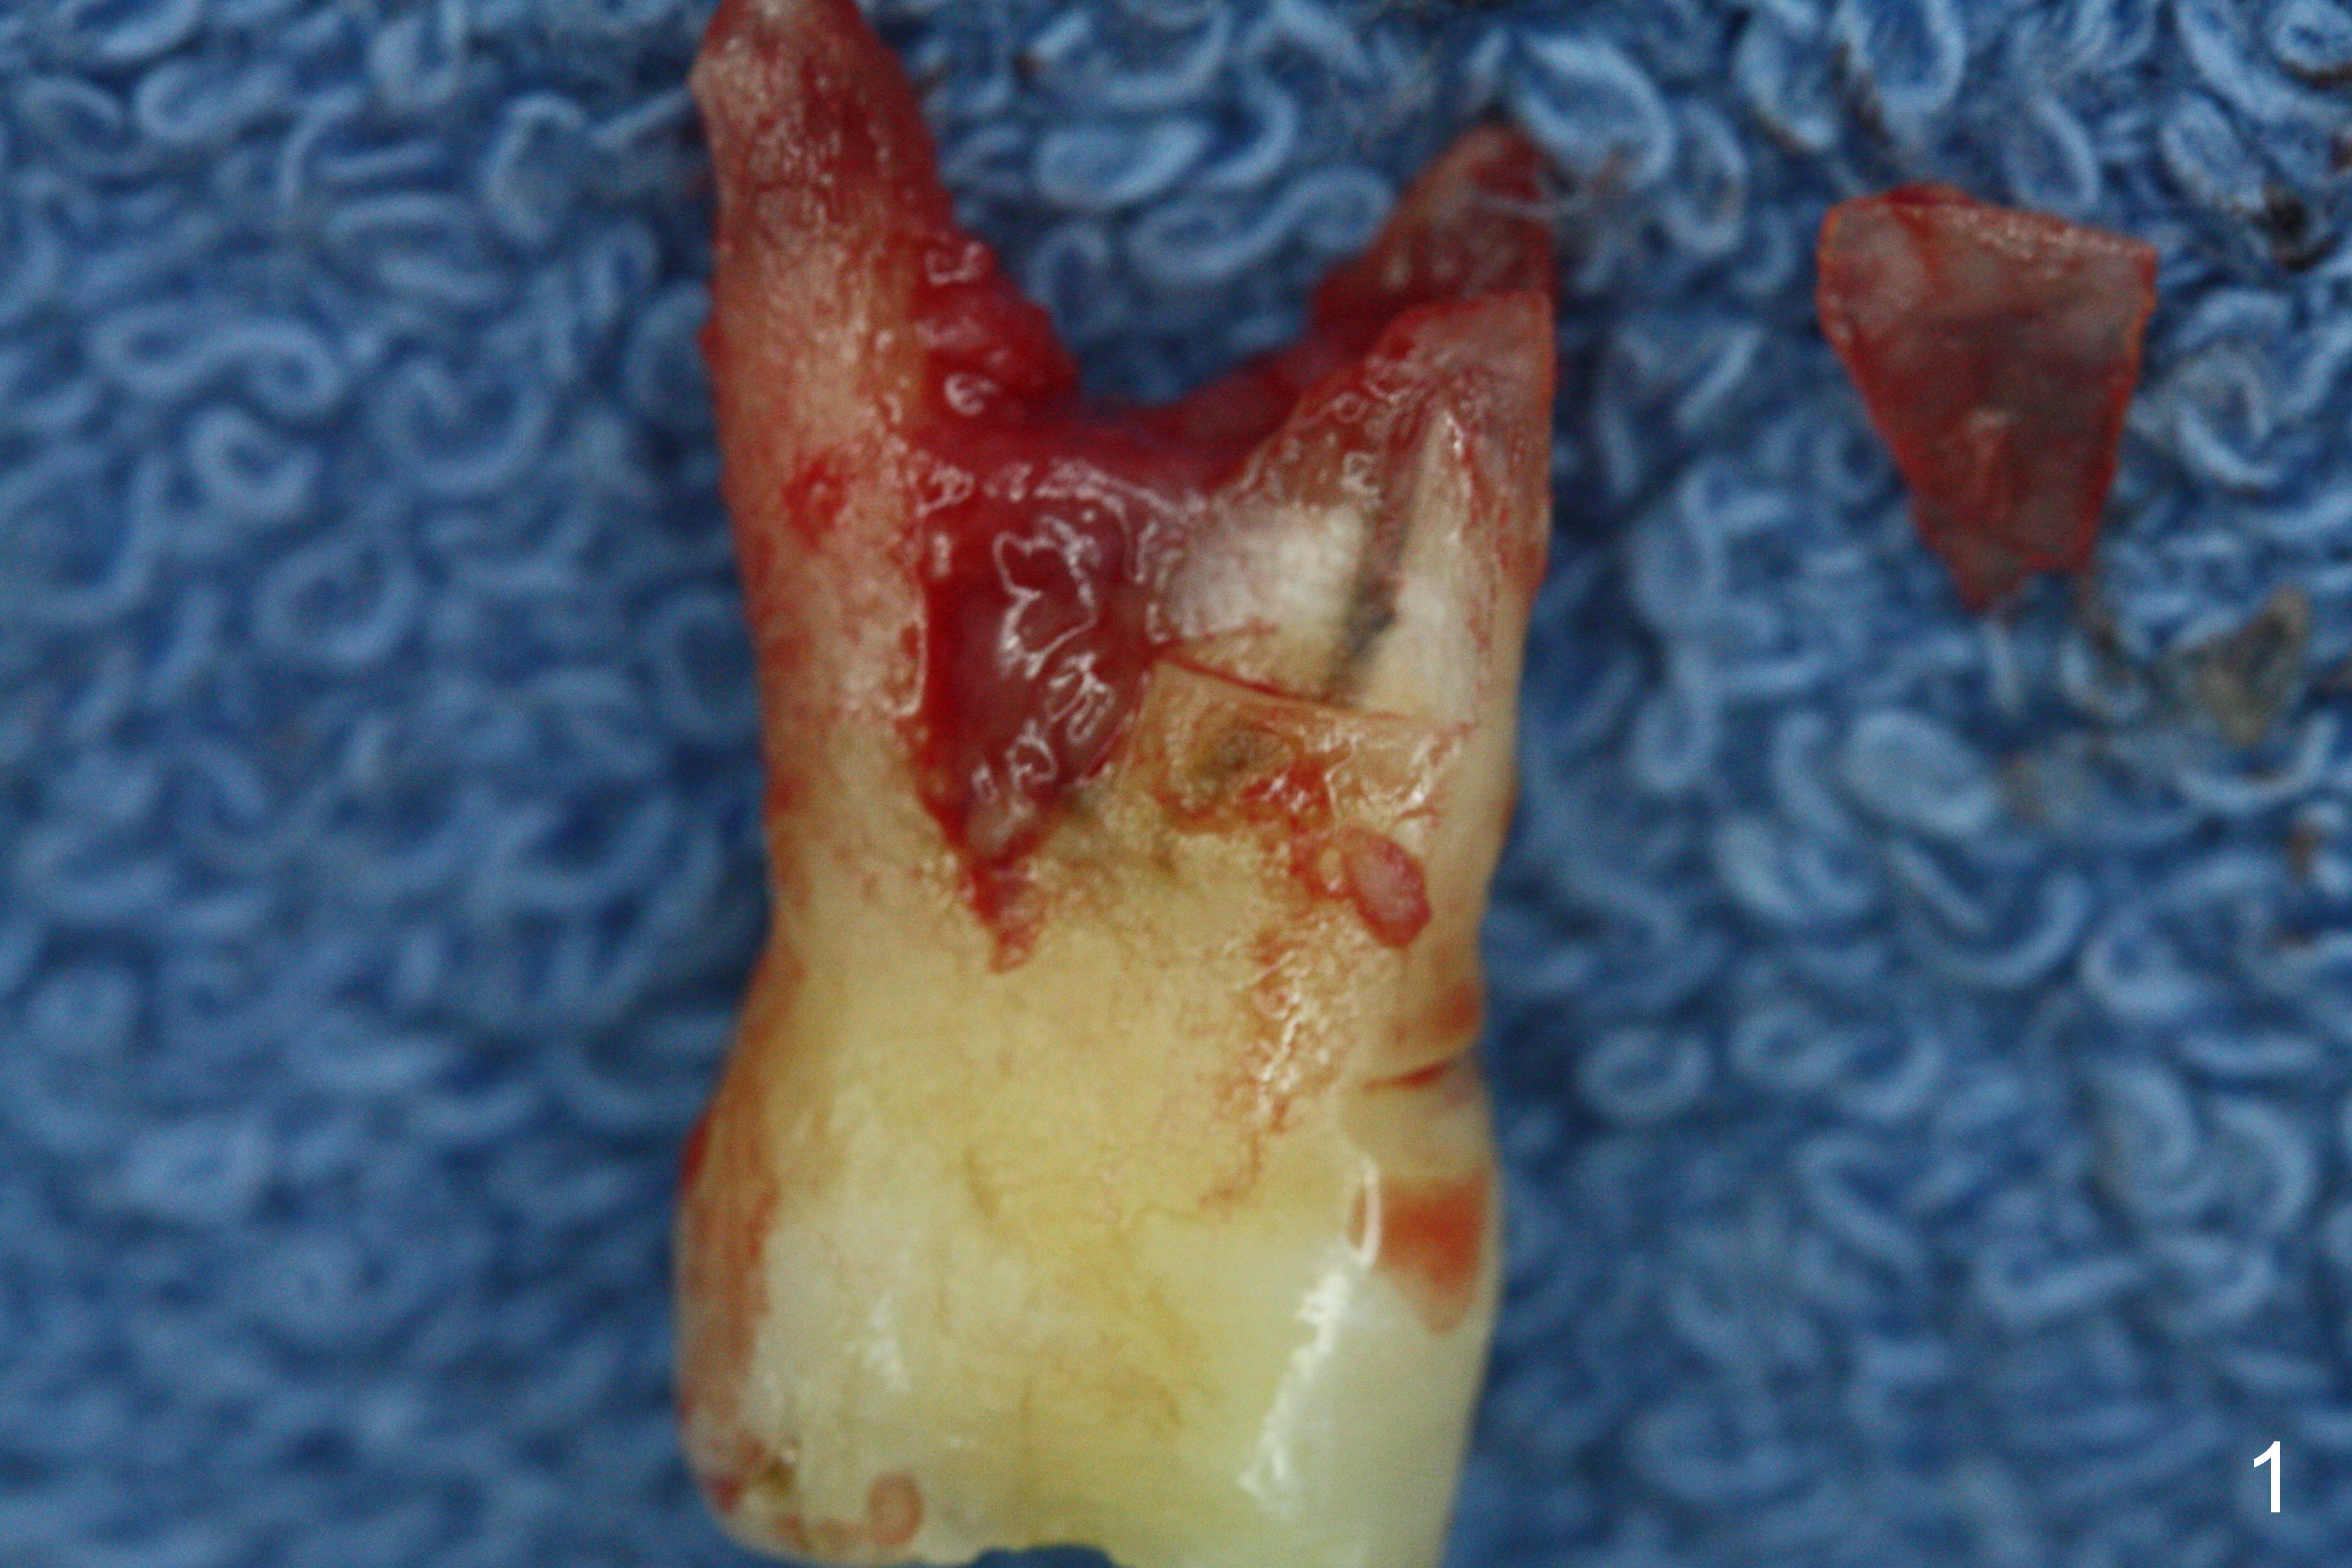

Preop exam show that the tooth #14 appears to be more severe than #18. When the former is extracted with forceps (not so easy), the mesial portion of the mesiobuccal root splits. The latter may be the reason for discomfort and one of the outcomes of advanced peridontitis. The septum is wide enough to use 4.3 mm Magic Drill (MD) following 1.6 mm pilot drill and Marking bur. A 5x13 mm IBS implant is placed apical to the mesial and distal crest and coronal to the septum (Fig.2,3). Insertion torque is ~ 35 Ncm. A 6.0x5.7(4) mm pair abutment is chosen over a 6.5 mm one, because the implant is placed somewhat distally (Fig.4,5). If the implant were placed more apically, the 4 mm cuff would be short for restoration. Allograft and autogenous bone harvested from the MD is placed around the coronal portion of the implant and the abutment cuff (*). Acrylic is spread around the abutment to hold the bone graft in place (without trimming).

The amount of the bone graft mesial and distal the implant seems to reduce 3 and 4 months postop, respectively (Fig.6,7 arrowheads). When the acrylic is cut off 4 months postop, the bone graft is loose. The gingiva is unhealthy. The abutment and implant are loose. A healing abutment is placed (5x4 mm). The implant is torqued to 35 Ncm 6 months postop with the healing abutment reapplied. The patient will return for follow up nearly 9 months postop. A larger healing abutment will be used if the implant is stable. Two weeks later, use a smaller restorative abutment for easy impression. In fact the implant is unstable with #15 mesial shift due to abnormal occlusion with #17 (Fig.8). Bone density around the implant is low (* in Fig.9 (PA), 10,11 (CT sagittal, coronal sections)). A healing screw is placed for self healing. A 2nd option is to remove the implant (Fig.12), BEB (Fig.13) and place the implant deeper (Fig.14) or larger one (5.5-6.5x13 mm). The 3rd option is to place larger and longer implants (Fig.15 (tapered), 16 (cylindrical)). The implant access has partially closed 14 months postop, but there is a small buccal opening with sanguine exudate. Incision reveals severe bone loss around the implant; the mobile tooth #15 is extracted (Fig.17). After debridement and irrigation with normal saline, Vera Graft (Fig.18 *) and Collagen plug are placed with periodontal dressing.